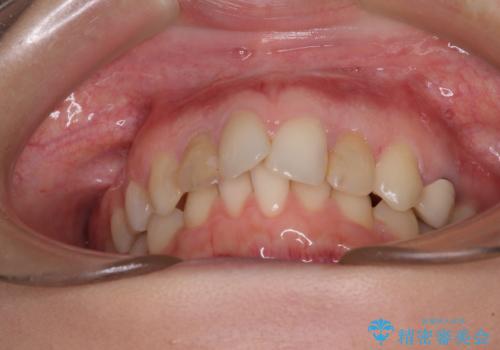

- 前歯の歯並びと神経を取って変色してしまった前歯を気にして来院された患者様です。

上下前歯の歯列不正はインビザラインにより整え、その後に、前歯2本をオールセラミッククラウンにて補綴治療することとしました。

下顎前歯が1本欠損しており、下顎歯列の大きさが本来よりも小さいため、上顎歯列とのバランスが悪く、深い咬み合わせになっていました。

上顎にIPRを多用して歯列の大きさを小さくするよう試みましたが、理想的な咬み合わせまでには改善させることはできませんでした。